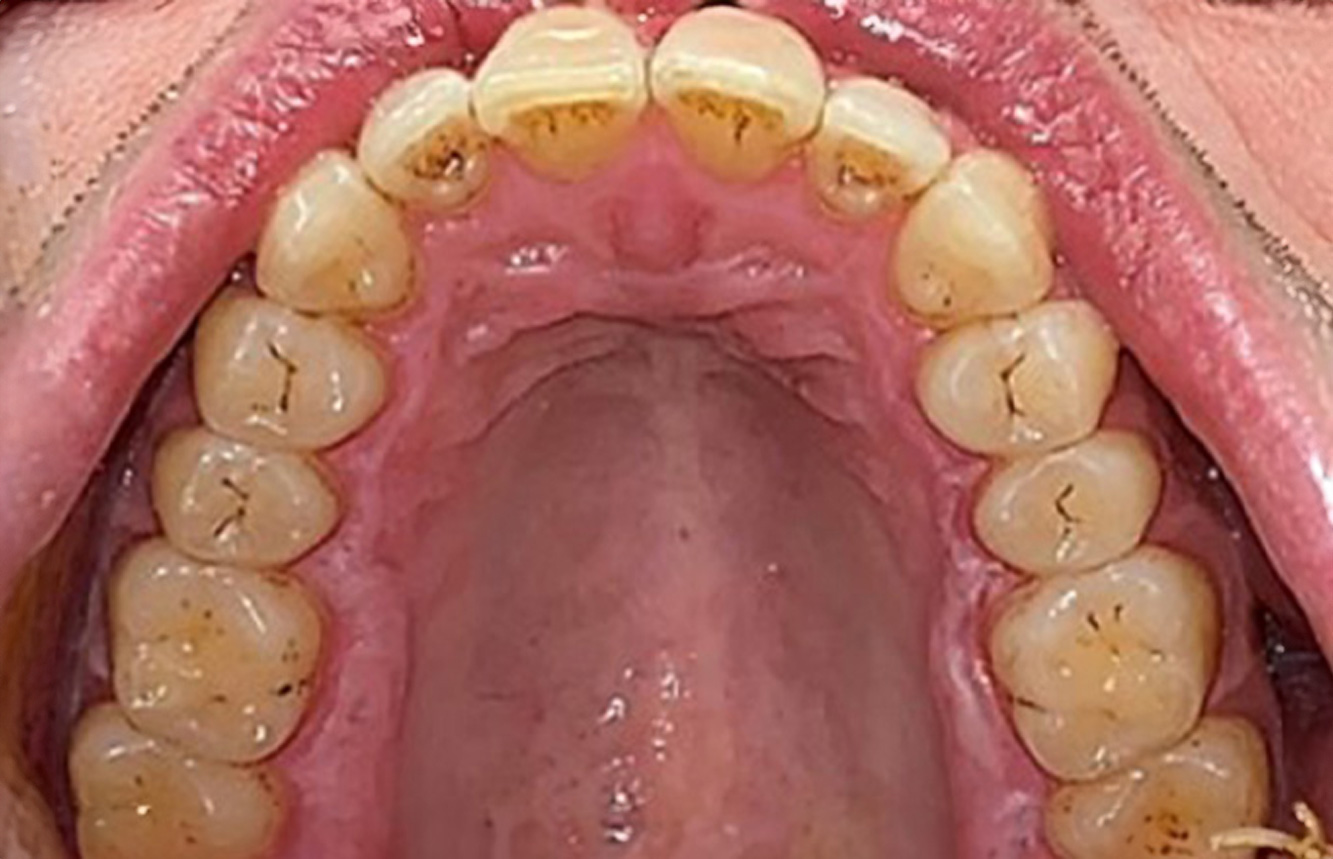

Patientenfälle nach IPCUm das Zusammenspiel der für den IPC definierten Bedarfs- und Risikofaktoren sowie die Auswirkungen einzelner Faktoren zu illustrieren, dienen nachstehende Fallbeispiele*. Die mundgesunde DiabetikerinEine 51-jährige mundgesunde Diabetikerin stellt sich zur Präventionssitzung vor. Die Blutzuckerwerte sind stabil bei einem HbA1c = 6,2%, folglich gilt sie mit dem entsprechenden Medikament Metformin (Antidiabetikum) als suffizient eingestellt. Die Patientin hat keine bestehenden Versorgungen oder orale Vorerkrankungen. Anhand der aktuellen Befunde lässt sich eine Gingivitis bei sonst stabilem parodontalem Zustand (Stage II, Grad B) feststellen. mehr Infos Fallpräsentation: Management komplexer ZahnprothetikEs ist längst bekannt, dass Mundgesundheit und Allgemeingesundheit in direktem Zusammenhang stehen und einen zum Teil bidirektionalen Einfluss aufeinander haben. Die Berücksichtigung beider Faktoren sind bei der Planung der oralen Prävention und Therapie der Patienten in der Zahnarztpraxis unabdingbar. Dabei ist oberstes Ziel, die Gesundheit und die Lebensqualität der Patienten sowohl aus zahnmedizinischer -und medizinischer Sicht zu erhalten. mehr Infos Der (mund)-gesunde Patient mit ImplantatenDer 55-jährige Patient gibt in der Anamnese an, keine Allgemeinerkrankungen zu haben und keine Medikamente einzunehmen. Die Lebensgewohnheiten des Patienten sind ebenfalls unauffällig. Der Patient hat einige zahnärztliche Restaurationen und zwei Implantate (2. und 4. Quadrant). Anhand der aktuellen Befunde lässt sich eine Gingivitis bei stabilem parodontalen Zustand am reduzierten Parodont (Stadium III, Grad A) feststellen. mehr Infos Der gesunde Patient mit parodontaler Vorerkrankung & PeriimplantitisEin 52-jähriger Patient stellt sich zur Präventionssitzung vor. Der Patient hat keine Allgemeinerkrankungen und nimmt keine Medikamente ein. Er hat verschiedene zahnärztliche Versorgungen und zudem zwei aktive kariöse Läsionen. Außerdem verfügt der Patient über vier Implantate (2., 3. und 4. Quadrant). Es zeigt sich eine parodontale Vorerkrankung (Stadium IV, Grad B). Derzeit herrschen stabile parodontale Verhältnisse, lediglich am Implantat regio 36 zeigen sich Sondierungstiefen (ST) von 5 mm. Zudem lässt sich eine Gingivitis feststellen. mehr Infos Der Diabetiker mit ParodontitisDieser Fallbericht eines 52-jährigen Mannes mit Typ-2-Diabetes und Parodontitis hebt hervor, wie durch individuelle Vorsorgemaßnahmen, die Gesundheit des Zahnhalteapparates erhalten bzw. das Fortschreiten der Erkrankung kontrolliert werden kann. mehr Infos Der 28-jährige Raucher mit ZahnerosionenDieser Fallbericht eines 28-jährigen Rauchers mit Zahnerosionen zeigt die Bedeutung personalisierter Patientenprofile. Er unterstreicht die Notwendigkeit, sowohl die Mundgesundheit als auch die allgemeine Gesundheit zu berücksichtigen, um Erkrankungen der Zähne bzw. des Zahnhalteapparates effektiv zu verhindern. mehr Infos Der Endokarditis-Patient mit aktiven KariesläsionenDer Patient ist 39 Jahre mit Z.n. Herzklappenersatz wegen Klappenfehlers und Endokarditis. Als Antikoagulans (Gerinnungshemmer) wird regelmäßig ASS 100 eingenommen. Aus dem Bereich Lebensstil ist die Ernährungsweise als kariesfördernd einzustufen, da mit hoher Regelmäßigkeit zuckerhaltige Lebensmittel sowie sechs bis sieben Mahlzeiten täglich verzehrt werden. Die Mundgesundheit des Patienten zeigt ein mittleres Kariesrisiko mit aktiven Läsionen. Das Parodontitisrisiko ist niedrig, es besteht eine Gingivitis. Es ergeben sich folgende Empfehlungen für die Prophylaxebehandlung. mehr Infos Die gesunde Patientin mit parodontaler VorerkrankungDie 68-jährige Patientin hat keine zahnmedizinisch relevanten allgemeingesundheitlichen Vorerkrankungen oder Medikation, auch aus dem Lebensstil ergibt sich kein besonderes Risiko. Die Patientin hat zwei Implantate (3. Quadrant, seit fünf Jahren) sowie eine parodontale Vorerkrankung (Parodontitis Stadium IV, Grad B) mit Zahnverlust. Derzeit zeigen sich stabile parodontale Verhältnisse. Für die Prophylaxesitzung ergeben sich vier Empfehlungen in den Bereichen Anamnese/Befund, Motivation/Instruktion, der Wahl der geeigneten Instrumente und für Resümee/Folgetermin. mehr Infos

NIWOP – No Implantology without PeriodontologyDer Transplantationspatient mit GingivawucherungenEin 71-jähriger Patient mit Z.n. Nierentransplantation und Hypertonie (Bluthochdruck) stellt sich vor. Bedingt durch die Krankengeschichte ist eine Dauermedikation mit Cyclosporin, zur Unterdrückung der Immunabwehr, und Amlodipin, zur Blutdrucksenkung, erforderlich. Außerdem berichtet der Patient über empfindliches Zahnfleisch und Zahnfleischbluten. Aus mundgesundheitlicher Sicht zeigt sich ein saniertes Gebiss mit acht fehlenden Zähnen, ausgeprägte Gingivawucherungen, eine Parodontitis Stadium II, Grad B mit aktiven Taschen und eine initiale Wurzelkaries an Zahn 22. In der Kariesrisikoabschätzung wird ein mittleres Kariesrisiko (API 60) festgestellt. Für die Prophylaxesitzung lassen sich folgende Behandlungsempfehlungen ableiten. mehr Infos * mit freundlicher Genehmigung von Dr. G. Schmalz und Prof. Dr. D. Ziebolz MSc. Download AreaProxeo Produkte